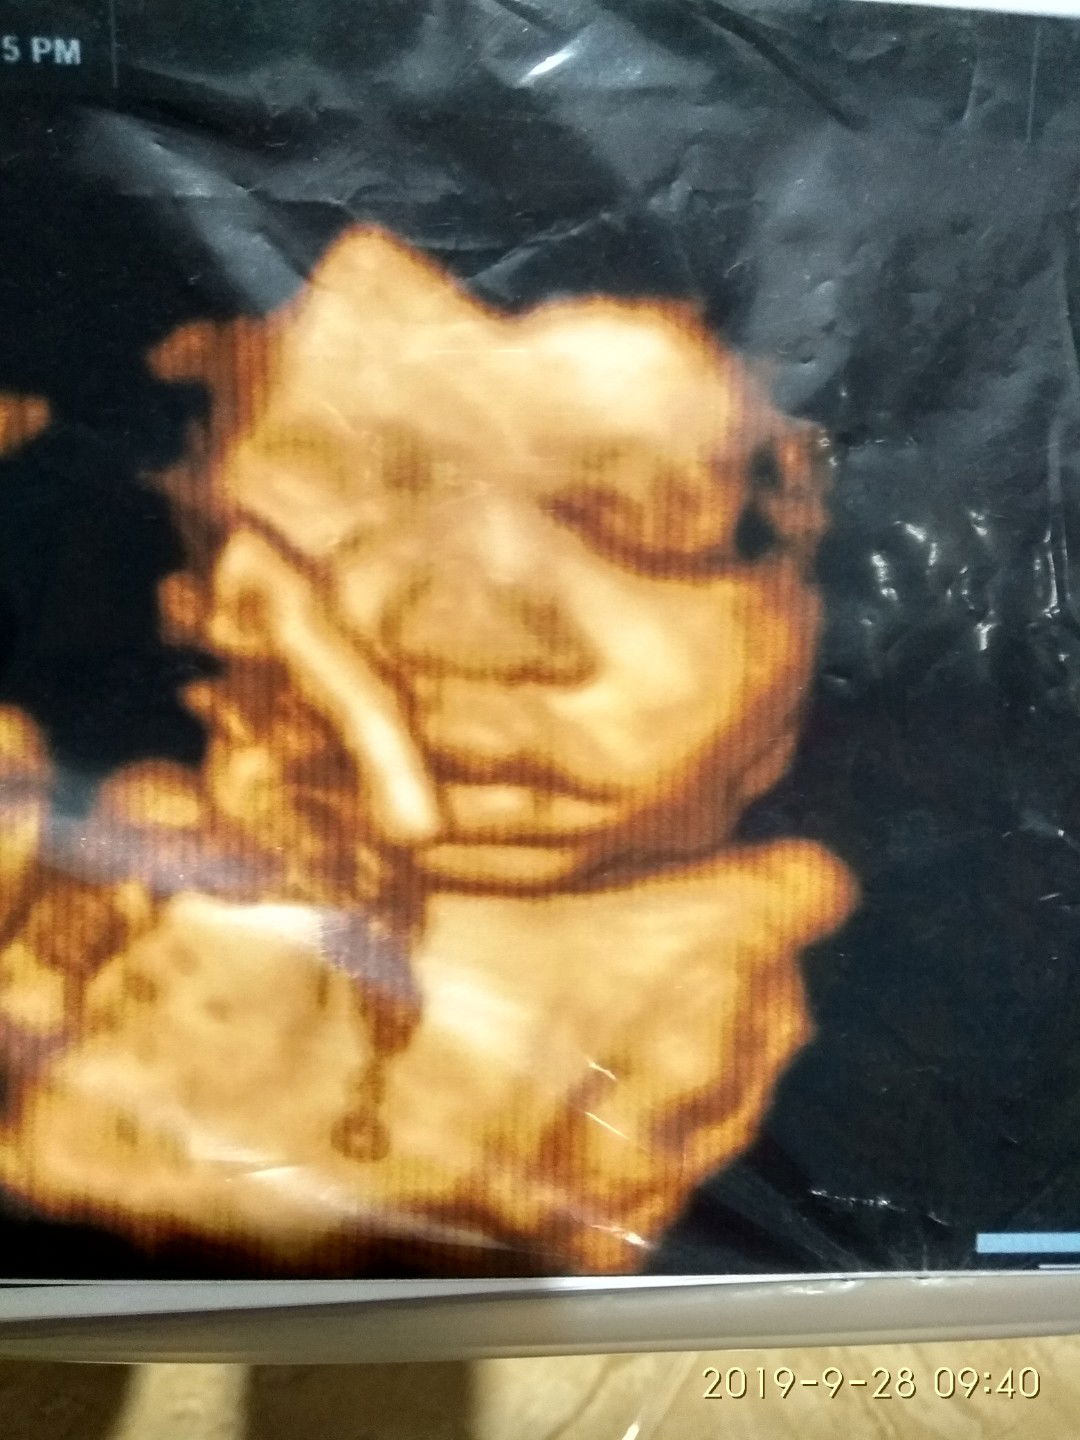

Hasil Ush

Bunda saya. Saya hamil anak pertama sdh nunggu 6 tahun alhamdulillah baru diberi amanah oleh Allah. Skrg ini kehamilan sdh 7 bulan. Saya sdh usg 2x, dan kedua hasil usg itu keliatan wajah bayi saya. Tapi mata kanan nya kok gak keliatan ya bunda. Sedangkan yg kiri keliatan jelas. Apa itu wajar dan bunda. Saya sering paranoid bunda. Mohon pencerahan nya..